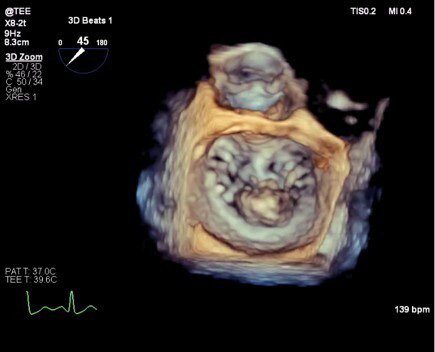

Advanced cardiovascular imaging has become indispensable for successful mitral repair, providing detailed anatomical and functional information essential for patient selection and procedural planning [72]. TEE remains the gold standard for intraoperative assessment, offering real-time evaluation of repair quality and immediate detection of complications. 3D TEE has significantly enhanced visualization of mitral valve anatomy and pathology, providing a comprehensive view of leaflet morphology and coaptation patterns [73] (Fig. 2).

Fig. 2.

Three-dimensional transesophageal echocardiography of the mitral valve.